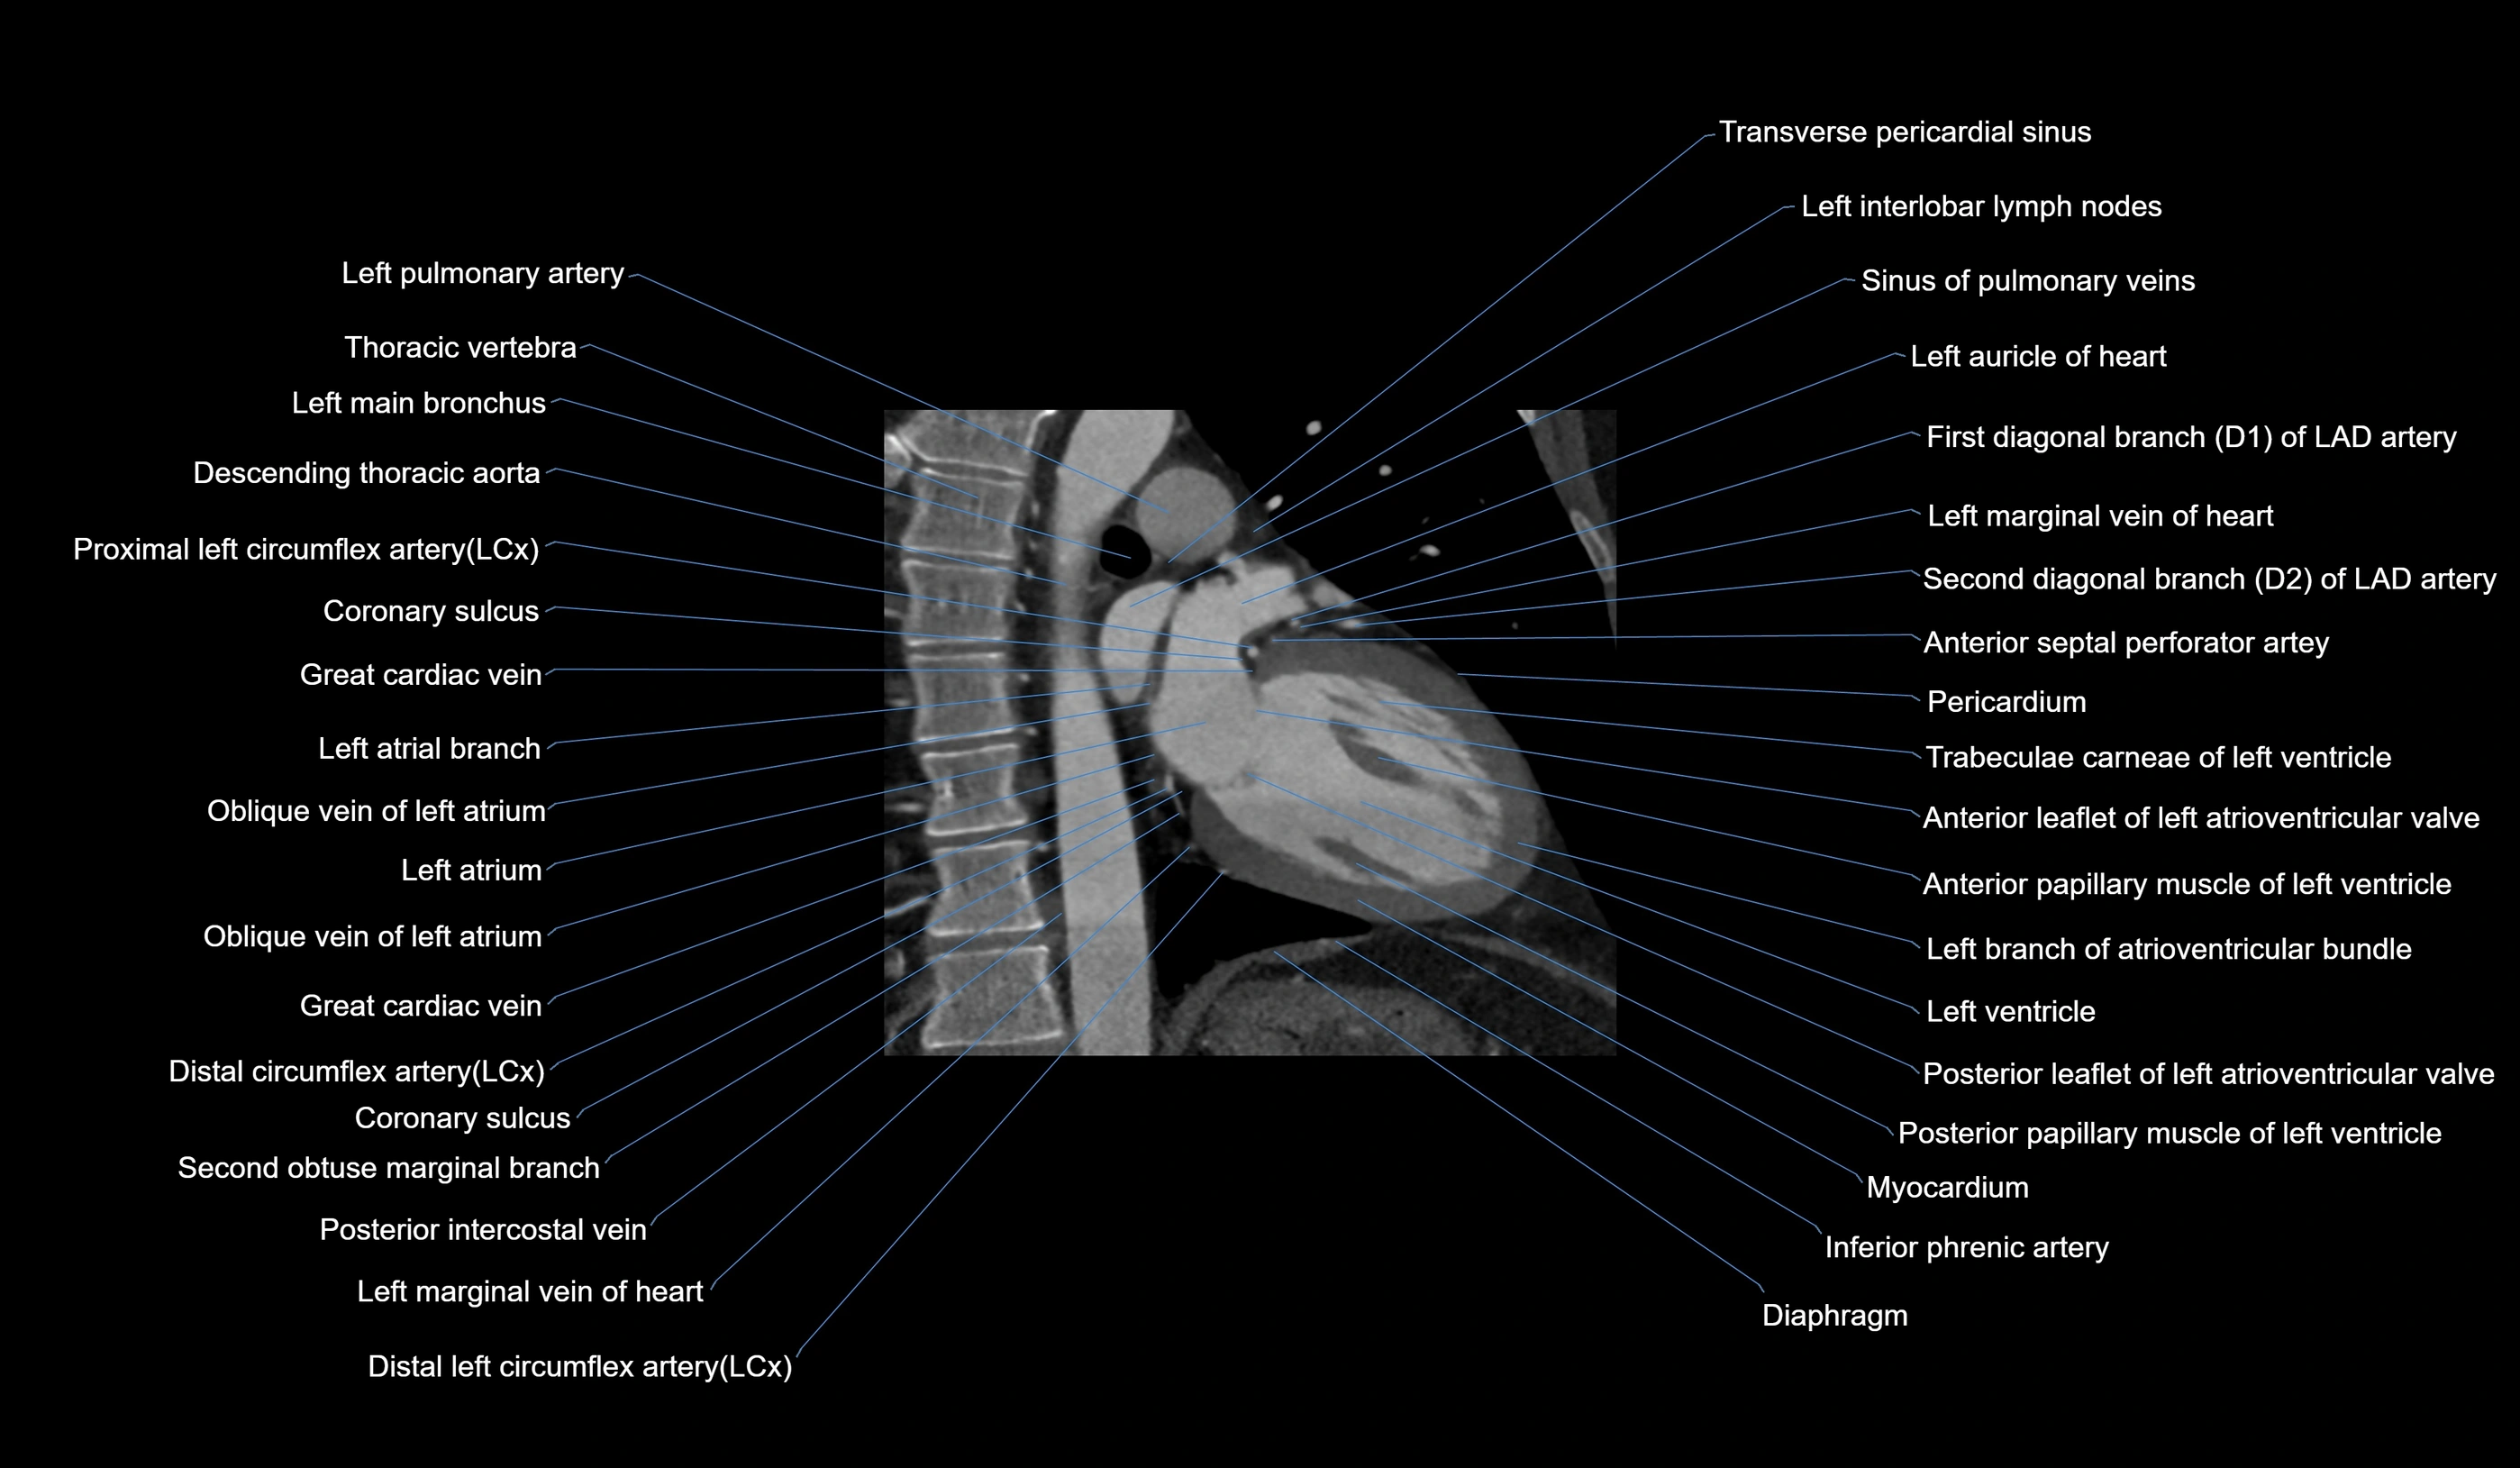

- First diagonal branch (D1) of LAD

- Left anterior descending artery (LAD)

- Left atrial branch (coronary artery)

- Left branch of atrioventricular bundle

- Left marginal vein

- Left pulmonary artery

- Left ventricle

- Myocardium

- Oblique vein of left atrium

- Posterior leaflet of left atrioventricular valve

- Second diagonal branch (D2) of LAD

- Transverse pericardial sinus

- Coronary sulcus

- Great cardiac vein

- Inferior phrenic artery